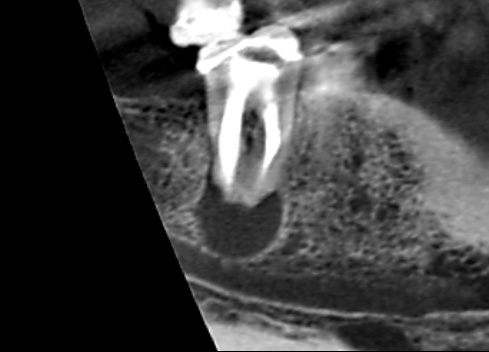

初診時のCT画像です。根の先に大きな膿の影がみられます。

赤い矢印の先は、膿が下顎管に接しているところです。膿としては、かなり大きい膿です。大きい膿は、根尖孔外感染という非外科的歯内療法では治りにくい膿になってしまっている可能性があります。患者さんは、できたら抜歯せずにご自身の歯をできるだけ使いたいとのことでした。

根管治療完了後の6ヶ月後のCT画像です。根の先にあった大きな膿が消失し、骨の再生がみられます。